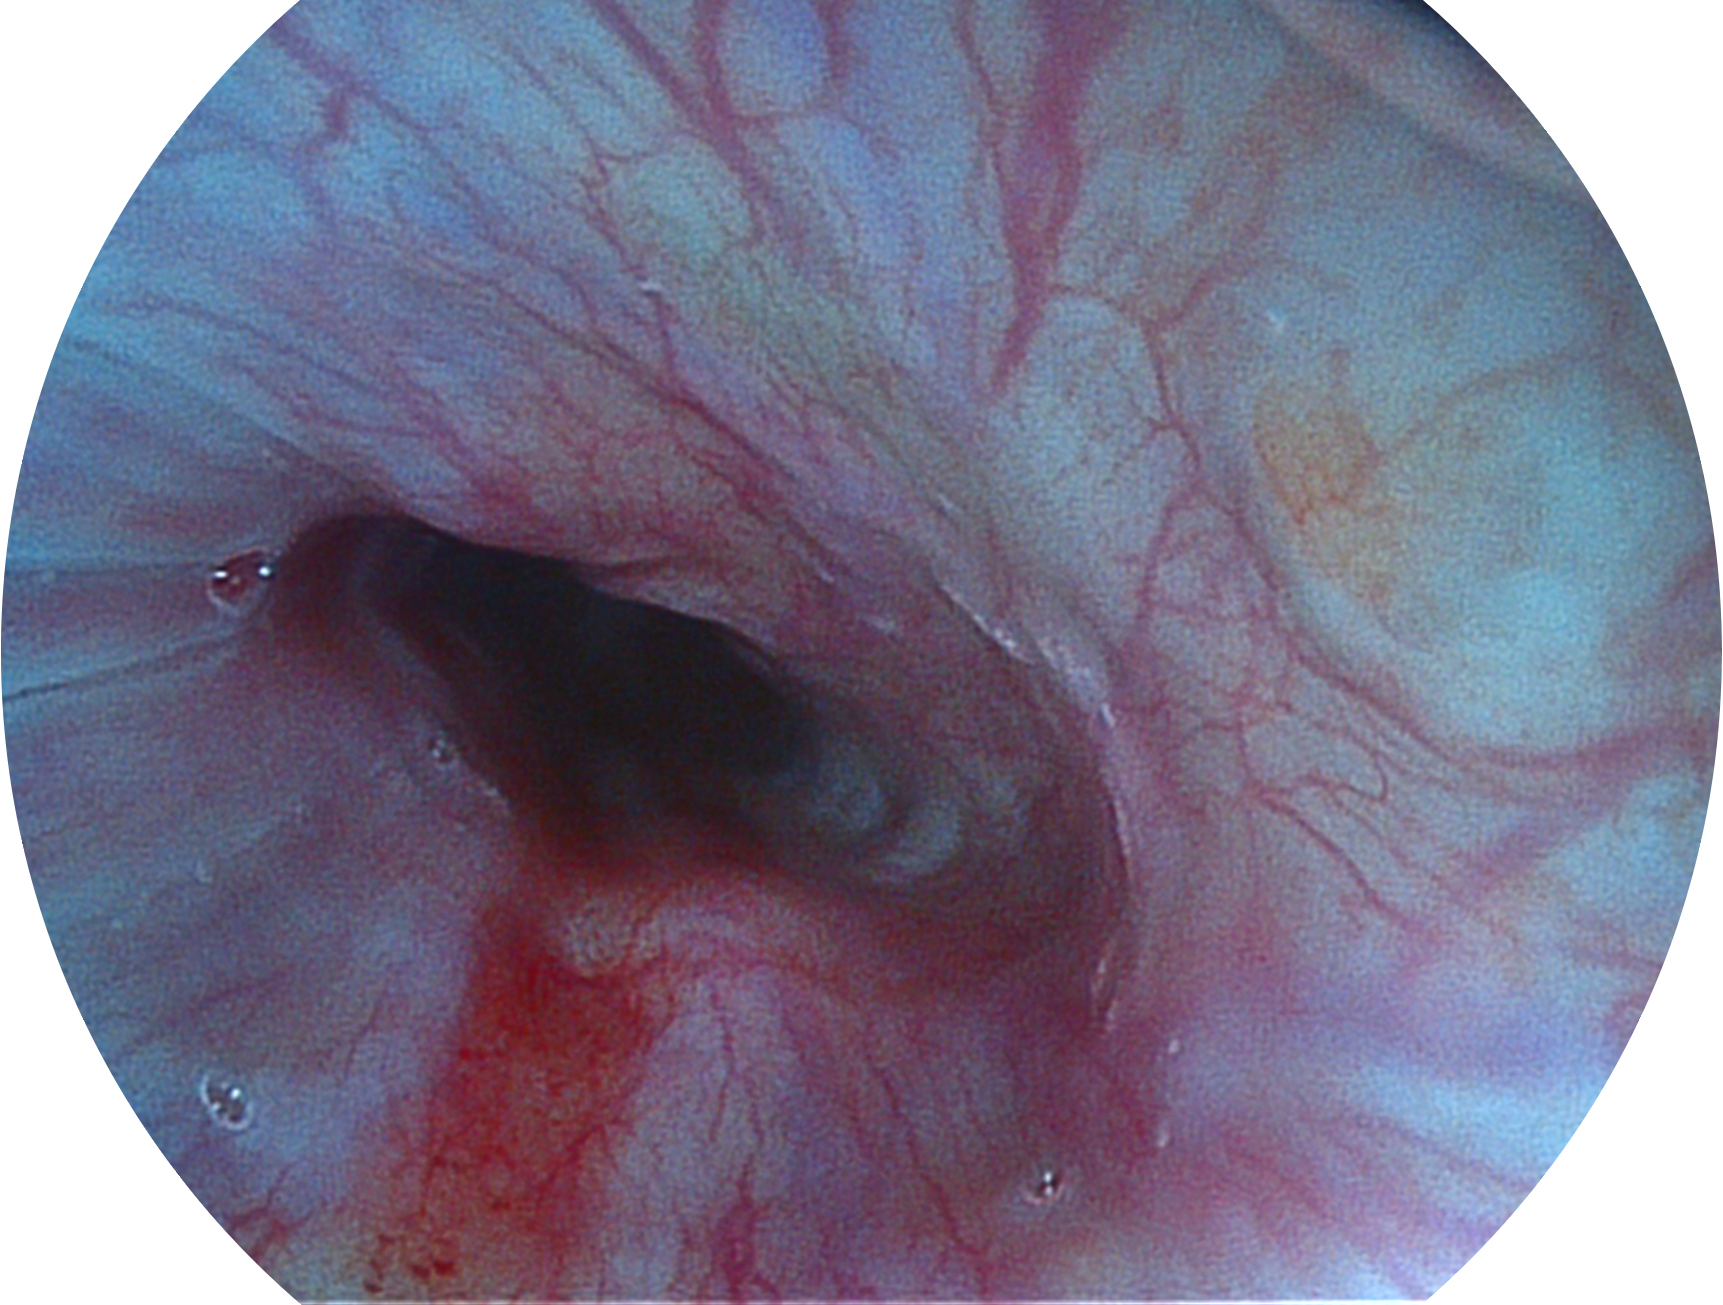

DB中国旗舰官方网站新开发的内镜染色技术,主要是基于多波长LED 光源的开发,VLS-55Q 四波长LED 光源是由四个不同颜色的LED光按照相应照明模式所规定的特定发光比例进行合束后形成,合束后形成的照明光的光谱由红光、绿光、蓝光及蓝紫光这四个不同的波段范围构成。具有更高光谱自由度,通过光谱比例的控制,实现了聚谱成像技术,英文全称为“Spectral Focused Imaging, SFI”,缩写为“SFI”和光电复合染色成像技术,英文全称为“Versatile Intelligent Staining Technology, VIST”,缩写为“VIST”。